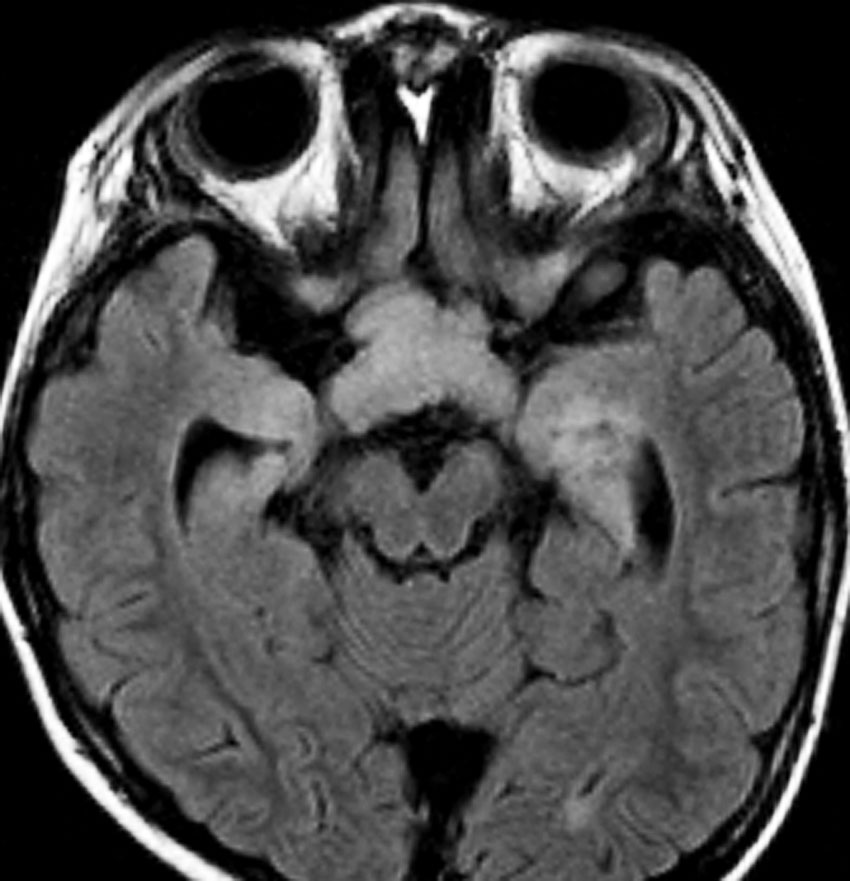

whole optic pathway pilocytic astrocytomaとは

両側の眼窩内視神経から視交叉、視索,外側膝状体,内包後脚,視放線近位部までが腫瘍化しています。FLAIRで高信号で,不規則にガドリニウム増強されます。これを手術摘出したり生検したりしても無駄です。放射線治療は不可能であり治療方法は化学療法のみです。

この子はCDDP/VCRの化学療法から開始して12年になりますが,今は無治療でわずかな視力ですが学校に通っています。優等生です。自然退縮を見ていますが,今後も変化する可能性はすこし残しています。